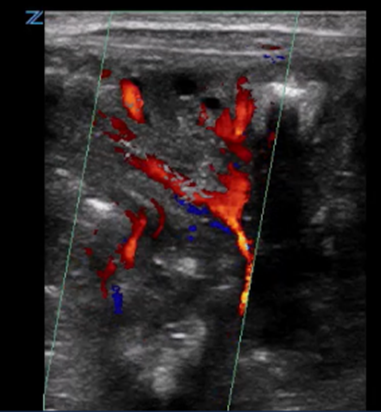

| Bowel wall ischemic gut injury by colour Doppler | |

| Strengths | Considerations |

|

![]() |

Colour speckling is not clearly identifiable |